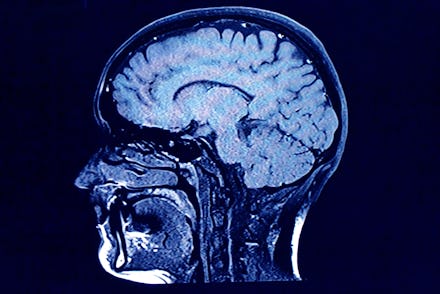

Schizophrenia, which occurs in around 1% of the U.S. adult population, is a "chronic, severe and disabling mental disorder characterized by deficits in thought processes, perceptions and emotional responsiveness," according to the National Institute of Mental Health. People with schizophrenia can experience a variety of debilitating symptoms, including visual and aural hallucinations and an aversion to social interactions.

C4 plays a role in a biological process called "synaptic pruning" — the severance of connections between neurons. That makes sense, a press release stated. Not only is synaptic pruning more prevalent during adolescence — the age when schizophrenia symptoms typically appear — but people with schizophrenia have been found to have fewer connections between neurons in their brains than people who don't have schizophrenia.